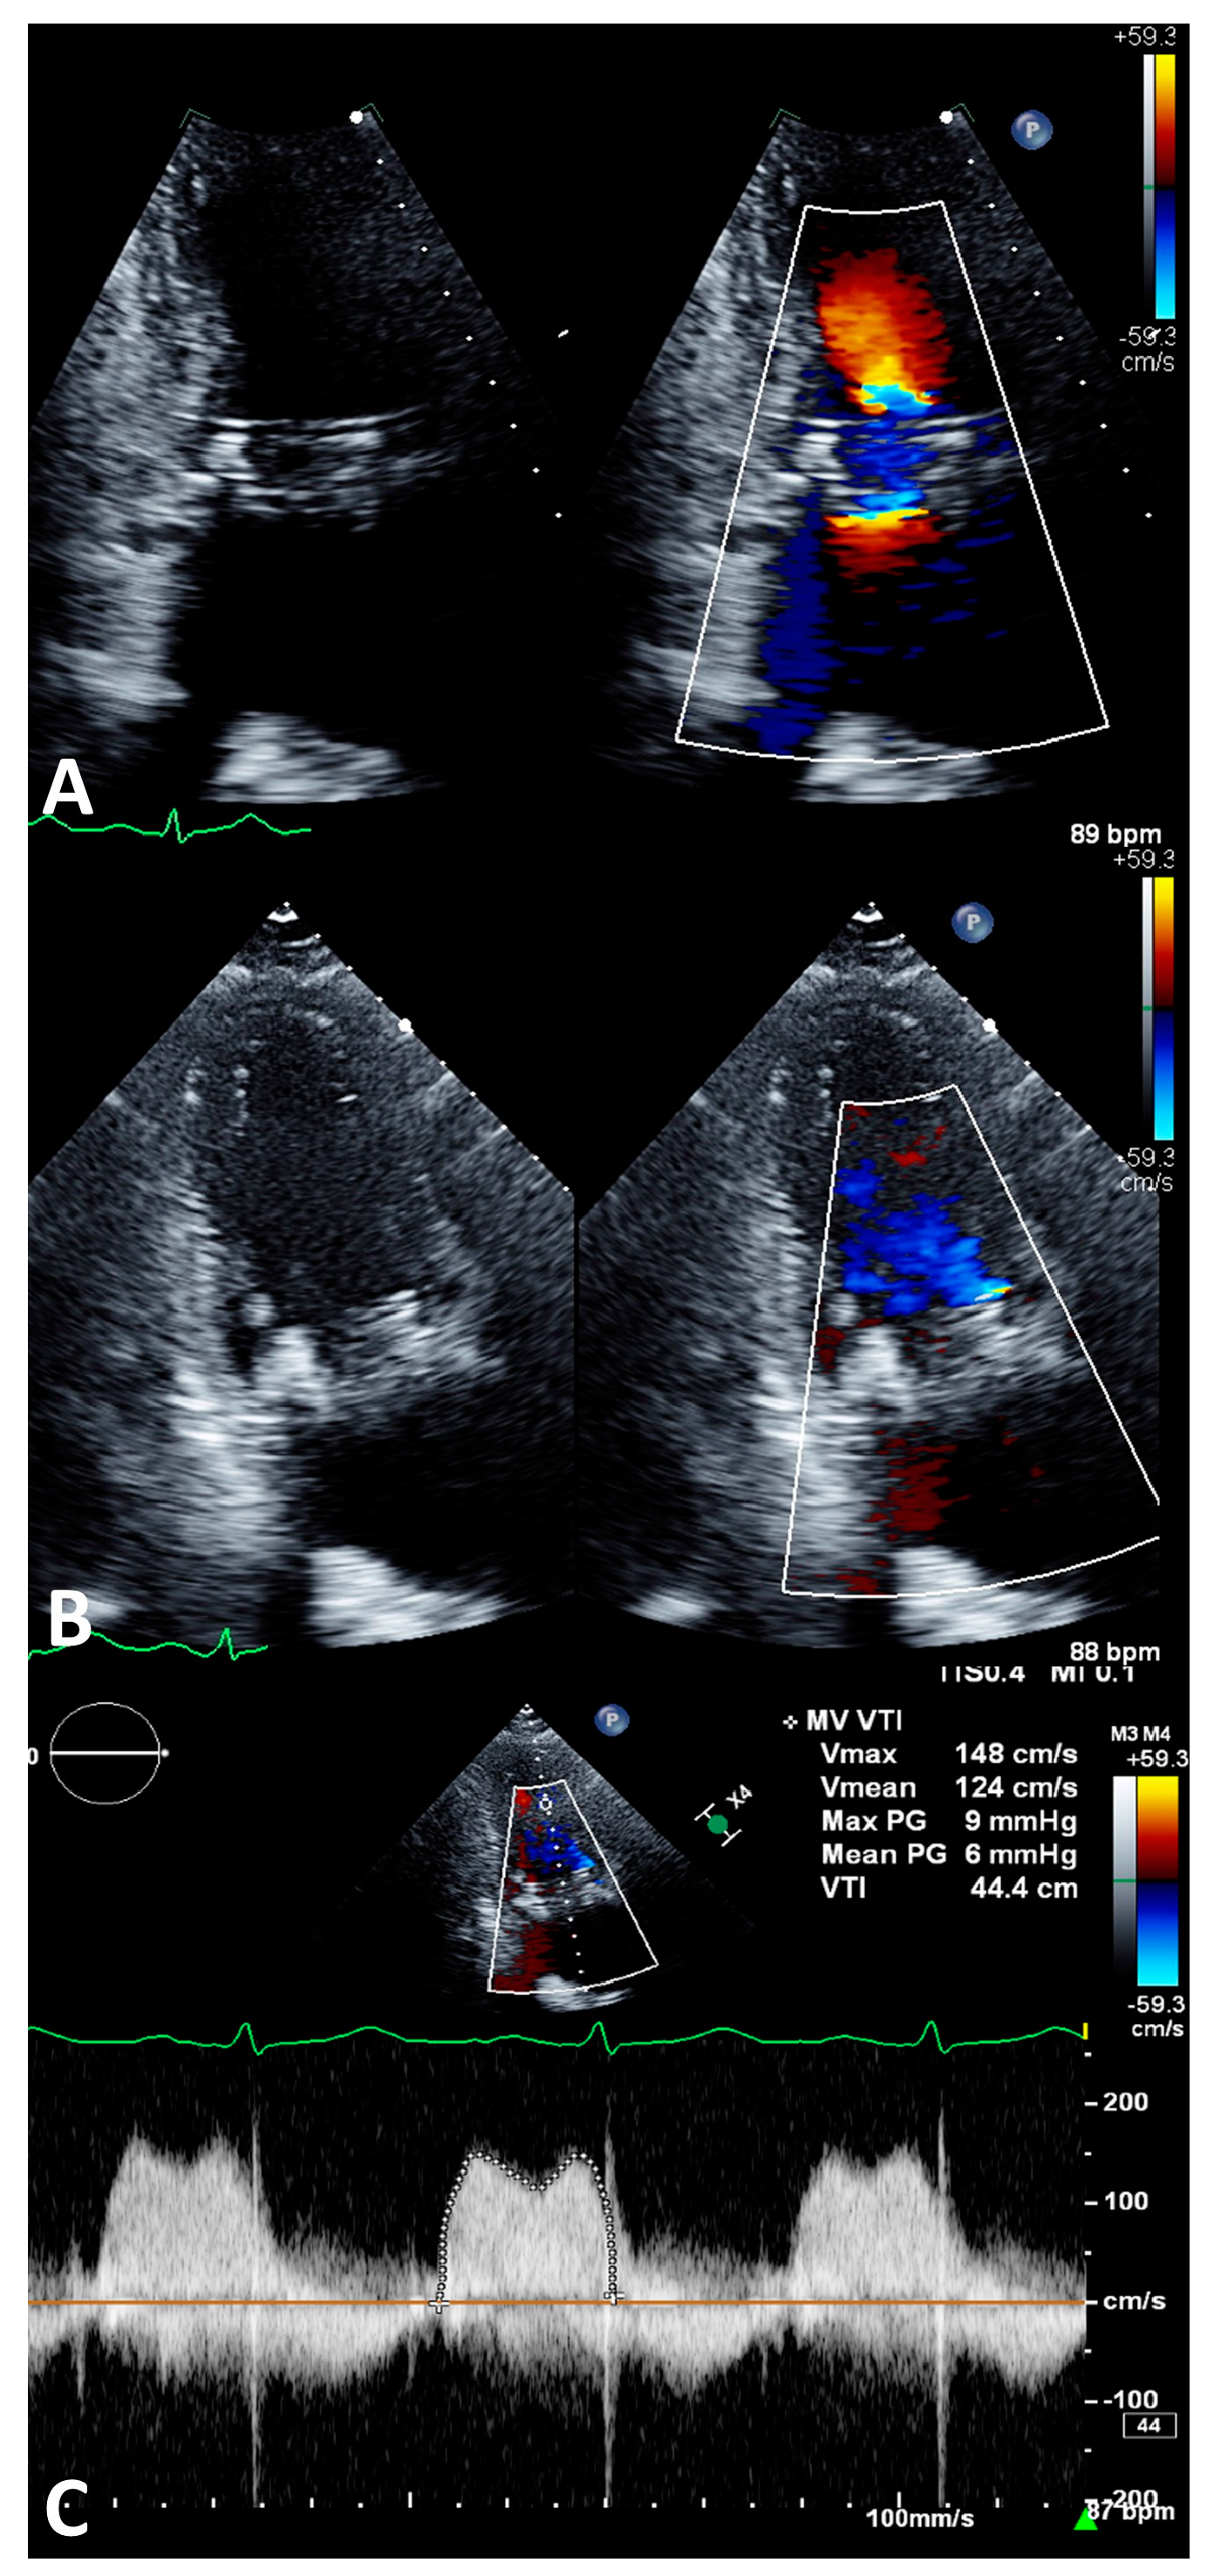

2.5. Imaging Evaluation

2.6. Procedure